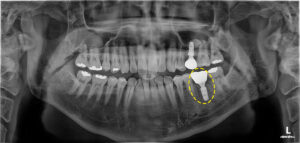

파노라마 사진을 살펴보면

유독 치아 뿌리쪽이 까맣게

보이는 부분을 보실 수 있는데요.

이는 염증으로 인해

잇몸뼈가 녹아 있는 모습이에요. 😥

이미 신경치료가 되어 있는 치아였지만

또 다시 염증이 발생하여

잇몸뼈를 상당히 녹인 상태였어요.

염증으로 인한 잇몸뼈의 소실로

치아의 흔들림이 있는 현재 상태에서는

치아를 살려 사용하기 어렵다고 판단되었어요.👨⚕️

이후 3D-CT와 구강 스캐너 등을 활용하여

모의 시술 과정을 걸쳐 임플란트의

위치와 기울기 등 선정하였으며,

그에 따라 네비게이션 가이드를

제작하여 오차 없이 예상했던 곳에

픽스처를 식립하였어요.🦷